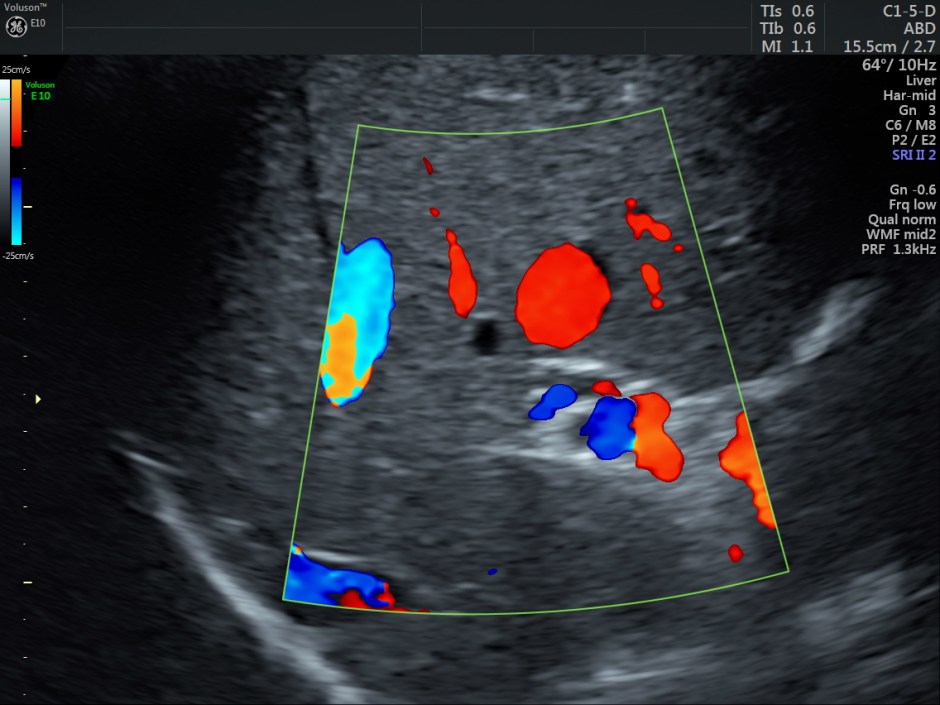

The venous flow is established by power doppler in the following pictures.

Reconstructed images show the feeding vessel and a vessel leaving the vascular structure.

STIC HIGH DEFINITION FLOW reconstruction images also show a feeding vessel and a vessel leaving the vascular structure,